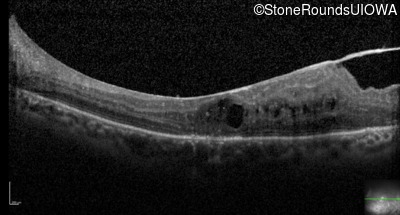

Optical Coherence Tomography - Right - 20/50 +2

Exemplar / OCT Stack

Optical Coherence Tomography - Left - 20/160